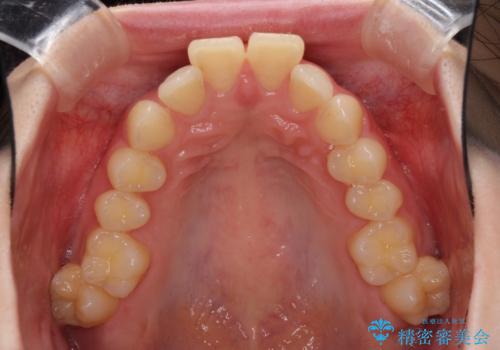

- 口元の突出感を気にして来院された患者様です。

左右ともに上顎奥歯が外を向き、下顎奥歯が内側に倒れているシザーズバイトであったため、補助装置により改善することとしました。

上下の咬み合わせは、下顎に対して上顎が相対的に前方にあったため、奥歯のシザーズバイト改善後に上顎左右第一小臼歯2本を抜歯し、上顎前突を改善していくこととしました。

左側の咬み合わせと上下正中の位置をコントロールするために時間がかかりましたが、事前に思い描いた通りの歯列に整い、患者様には大変満足していただきました。